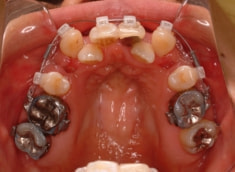

治療前

修復歯、補綴歯もあります。下顎8番が水平埋伏しています。